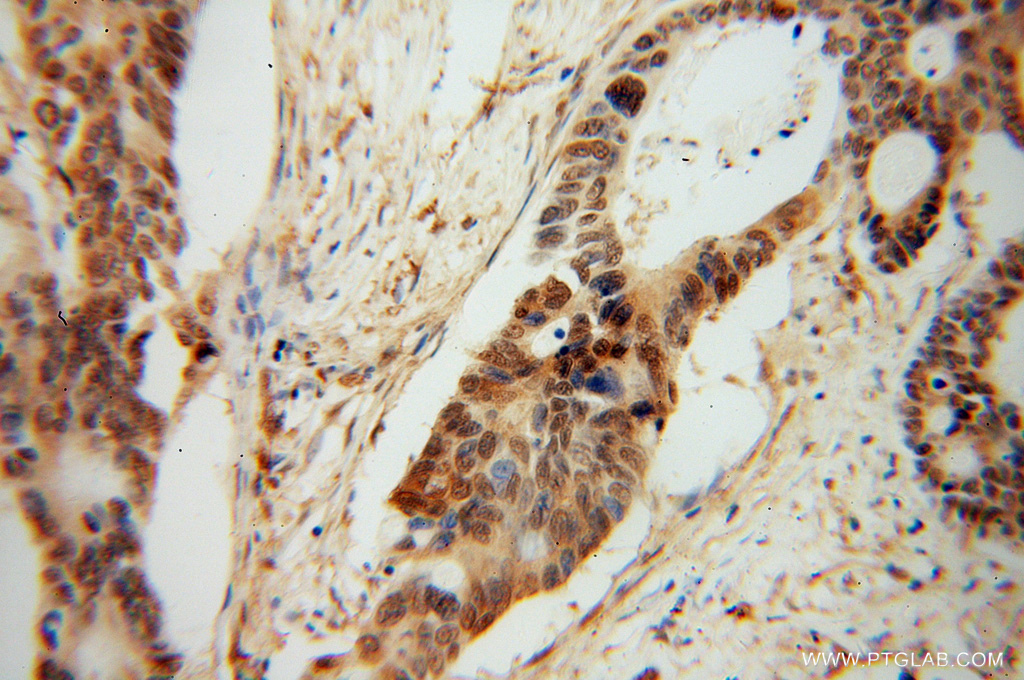

| Positive IHC detected in | human colon cancer tissue Note: suggested antigen retrieval with TE buffer pH 9.0; (*) Alternatively, antigen retrieval may be performed with citrate buffer pH 6.0  |

| Immunohistochemistry (IHC) | IHC : 1:20-1:200 |